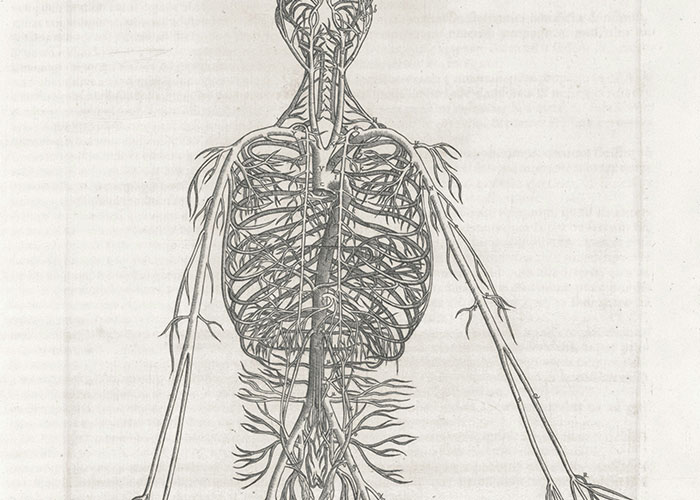

The human body contains about 60,000 miles of blood vessels. If you laid them all out end to end, they could circle the Earth more than twice.

The human body contains about 60,000 miles of blood vessels. If you laid them all out end to end, they could circle the Earth more than twice.

I’ve always wanted to go around the world- I guess this will have to do!